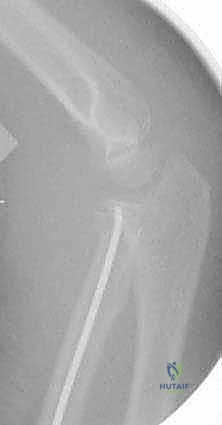

صورة شعاعية تظهر التثبيت النهائي للكسر باستخدام الأسلاك المعدنية المتقاطعة لضمان الاستقرار التام.

لفهم مدى الدقة التي تتم بها هذه الجراحات في صنعاء، نستعرض خطوات تقنية الرد عبر الجلد (Percutaneous Pinning) خطوة بخطوة:

- التحضير والتخدير: يتم تخدير الطفل كلياً لضمان عدم الحركة والألم. يتم تعقيم كامل للذراع وتغطيتها بالمفارش الجراحية المعقمة.

- التموضع (Positioning): يوضع ذراع الطفل على طاولة شفافة للأشعة، مما يسمح باستخدام جهاز التنظير الإشعاعي (Fluoroscopy) بحرية تامة من جميع الزوايا.

- تحديد نقطة الدخول الآمنة: لتجنب إصابة العصب (PIN)، يقوم د. هطيف بوضع الساعد في حالة كب كامل (Full Pronation).

- إدخال الأسلاك (Pin Insertion): يتم إدخال سلك كيرشنر (K-wire) بقطر مناسب (غالباً 1.5 مم إلى 2.0 مم) عبر الجلد، من الجانب الخارجي للمرفق، مروراً برأس الكعبرة، وعبر صفيحة النمو، وصولاً إلى عنق الكعبرة لتثبيت الكسر.